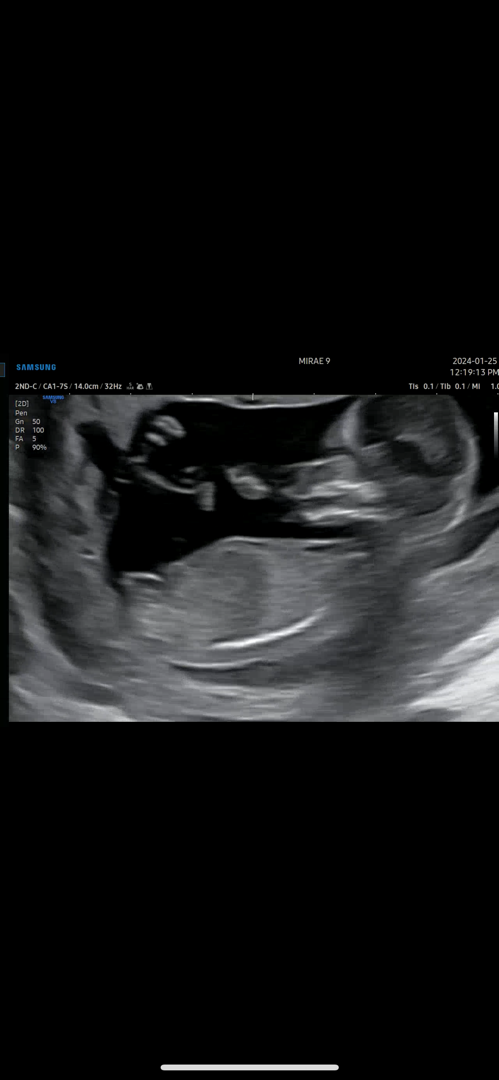

12주5일 초음파입니다~~ 16주에 알려주신다고 하셨는데 궁금해서 올려봅니다!

각도법 봐주세요~~❤️